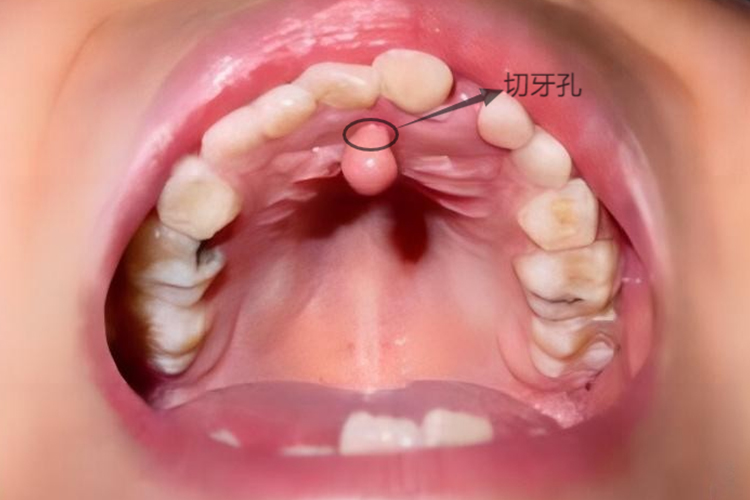

正中囊肿与鼻腭囊肿区别主要在于发病部位的不同,正中囊肿位于切牙孔之后,腭中缝的任何部位,少部分可发生于下颌正中线处。鼻腭囊肿来自切牙管残余上皮,位置较正中囊肿靠前。